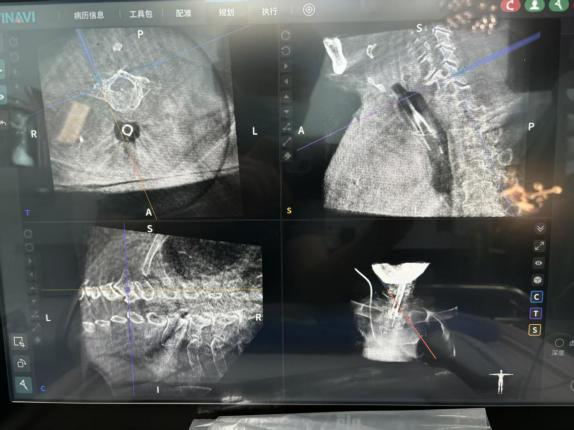

凭借机器人的亚毫米级的稳定性和三维空间精准定位能力,完美突破了传统手术的局限。

术前,机器人为每一枚椎弓根螺钉的置入规划最优路径,打造精准手术“蓝图”;术中,实时导航辅助操作,全程监测、调整螺钉置入方向,从矢状位、冠状位、轴位多维度把控置钉角度,有效规避了神经、血管损伤的风险,大幅降低了手术潜在风险。

同时,机器人还能实现术中即刻扫描,螺钉位置清晰可见,彻底解决了传统透视的遮挡难题。

通过与骨科手术机器人配合,整个手术过程顺利完成,螺钉置入位置精准无误,患者术中出血量大幅减少,手术时间也得到有效优化,手术效率和安全性实现双重提升。